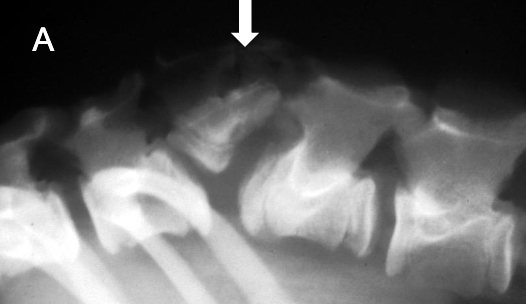

What is shown in this image?

hemivertebra